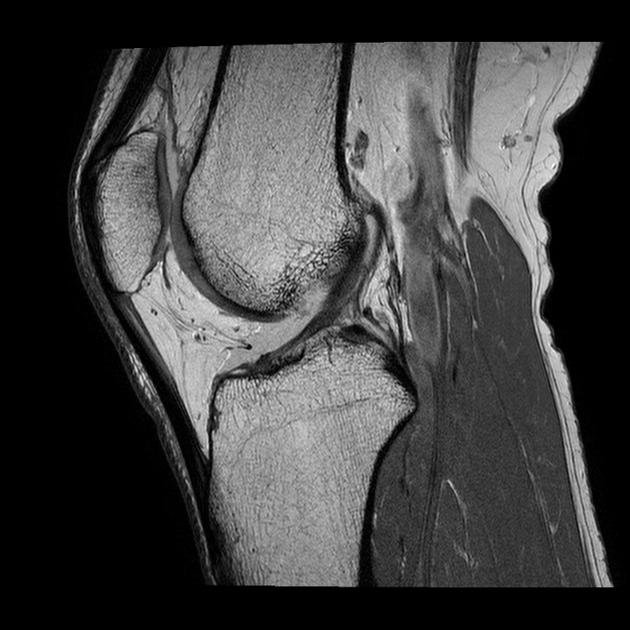

Knee MRI

MRI images are black and white. Abnormalities may appear as bright white spots. These indicate areas where the contrast dye has collected due to enhanced cell activity.